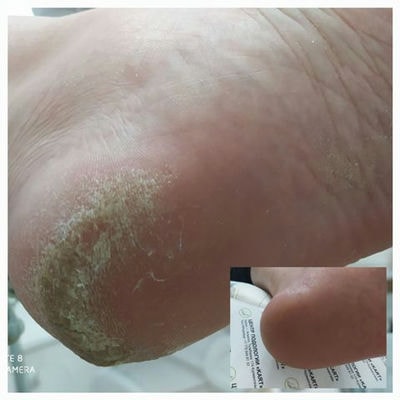

Безболезненное, безмедикаментозное решение целого ряда подологических проблем:— Коррекционые системы для вросших ногтей без хирургического вмешательства- Безопасный препаратный педикюр для диабетической стопы- Индивидуальный подход к восстановлению грибковых заболеваний кожи стопы и ногтей- Удаление и лечение натоптышей, мозолей, бородавок- Лечение онихолизиса (отслоения ногтевой пластины от ногтевого ложа)- Коррекция поврежденых и деформированых ногтей- Восстановление эпидермиса кожи стопы (сухость кожи стоп, трещины на пятках)